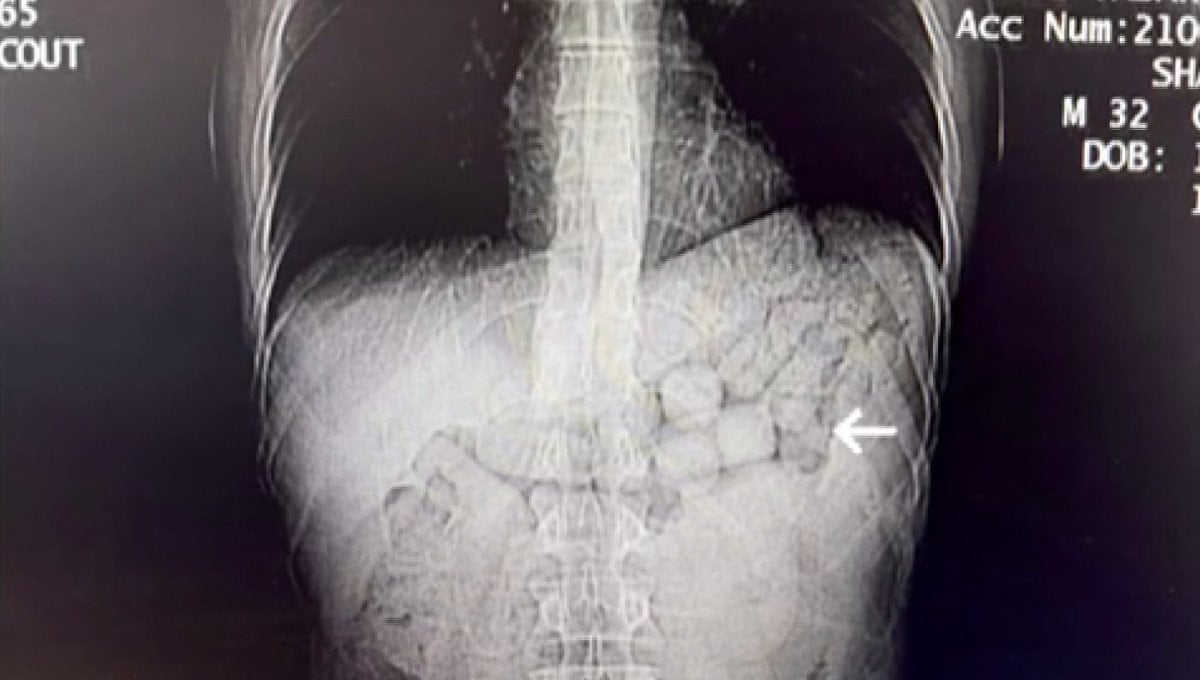

Şüphelilerin yutma yöntemiyle uyuşturucu taşıdığı değerlendirilince, hastaneye sevk edildi. Şüphelilerin çekilen tomografi görüntülerinde; mide ve bağırsak bölgelerinde yabancı cisimlere rastlandı.

3 gün süren kontrollerin ardından şüphelilerden, müdahaleyle 91 kapsül halinde 807,15 gram metamfetamin çıkarıldı.